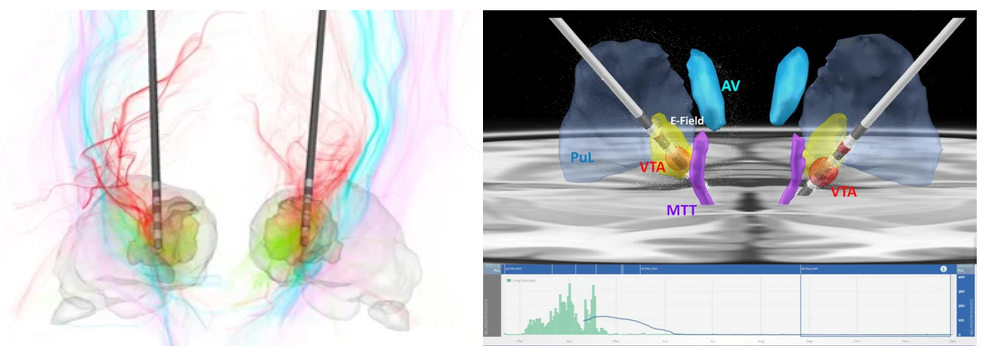

Thalamic nuclei are increasing targeted for deep brain stimulation (DBS) applications and for ablation using focused ultrasound (FUS). The earliest use is targeting the ventral intermediate (VIM) nucleus for treatment of essential tremor using both DBS and FUS. The methods we have developed for visualization and segmentation of thalamic nuclei (see sections below) have been helping neurosurgeons with accurate targeting of these deep brain nuclei. Top left is a recent use of the THOMAS algorithm for DBS of the centrolateral (CL) nucleus for traumatic brain injury reported by Schiff et al. Top right panel shows the use of THOMAS to visualize the targeting of centromedian (CM) nucleus for epilepsy by Ganne et al. The bottom EEG recording shows dramatic reduction in seizures following implantation of DBS electrodes in CM.